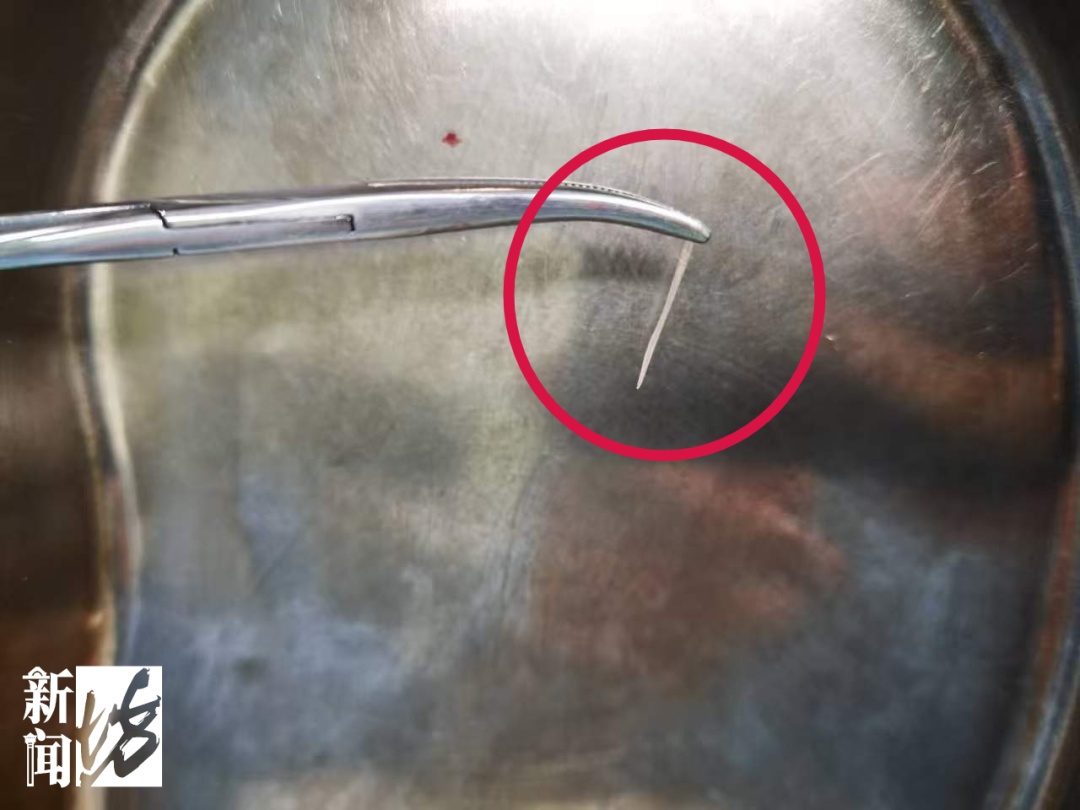

随即,在麻醉科和手术室团队的保障下,张女士被送入手术室。经过细致探查,医生最终在甲状腺左叶上极附近找到并成功取出鱼刺,长度约1.7厘米。随后,手术团队对食管穿孔区域进行规范处理,并清理周围炎性组织,值得一提的是,此次手术仅用了30分钟便顺利完成。